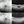

However, use of MEK inhibitors may lead to ocular side effects, including self-limited, multifocal, serous-like retinal detachment.1 This side effect has previously been described as a variation of a multifocal serous chorioretinopathy, but has since been more accurately named MEK inhibitor-associated retinopathy (MEKAR).1 As retina specialists continue to explore MEKAR and its similarities to central serous chorioretinopathy, it is becoming clear that these are two distinct pathologies. MEKAR is predominantly bilateral and multifocal, with fluid accumulating in nongravitational, rounded globules without fluid tracking or guttering (Figure).1

The symptoms of MEKAR are similar to those reported in patients with central serous chorioretinopathy. Interestingly, only 48% of patients in the study reported visual symptoms, the most common being blurry vision, although 83% of eyes had fluid foci involving the fovea.1 Other symptoms include metamorphopsia, seeing a bubble or “doughnut” shape, and the sensation of an “orange glow” around objects.1 MEKAR was also found to have a mild effect on visual acuity, although no eye lost more than 2 lines of Snellen VA.1 Because MEK inhibitors are typically life-extending medications, they are rarely discontinued, but screening for this possible side effect is critical to help patients make educated decisions about their care.